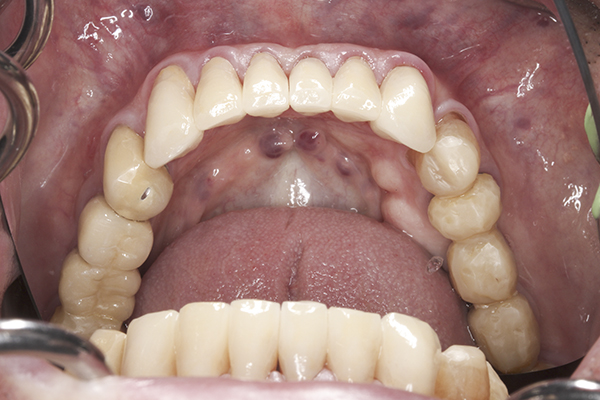

(15.) Preoperative maxillary, occlusal view.

Figure 15

(41.) Postoperative maxillary occlusal view. Note the composite tops on teeth Nos. 12 through 14.

Figure 41